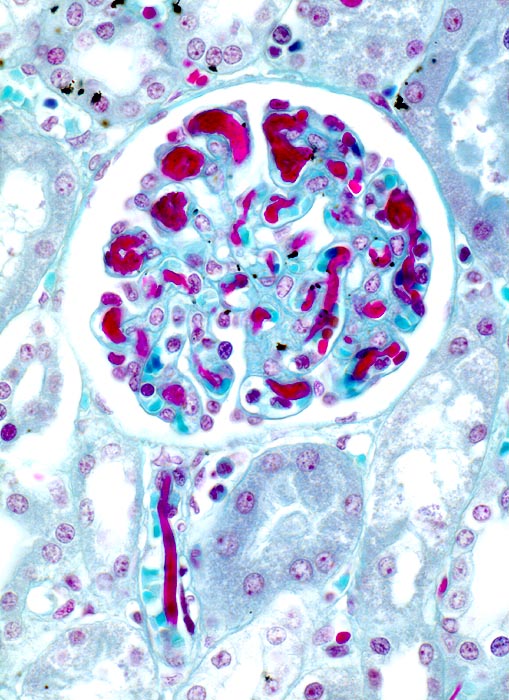

• Rote Fibrinthromben in Kapillarschlingen der Glomerula, Vas afferens und efferens, peritubulären Kapillaren. Das sollte der Kliniker dem Pathologen mitteilen:

• Grunderkrankung, die zu DIC führen kann.

• Gerinnungsstörung (Blutungstendenz, Thrombosen, Organdysfunktion, veränderte Gerinnungsparameter).